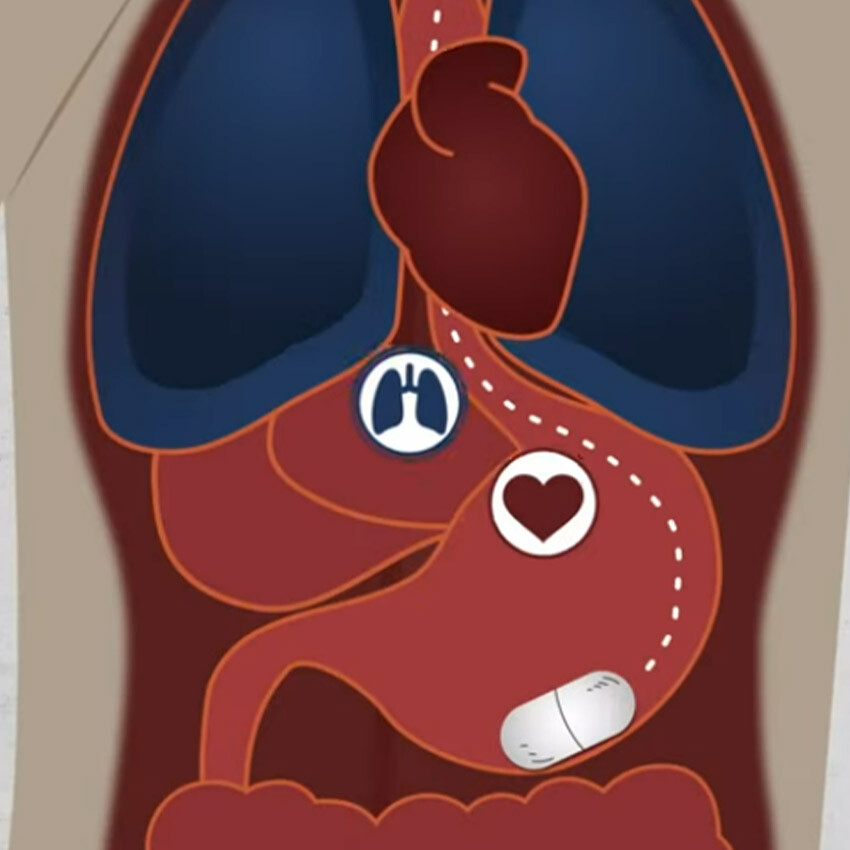

Araştırmacılar, hastalıkların tespitinde işe yarayacak olan bir kapsül geliştirdi. Üstelik bu kapsül, bir ilaç gibi yutulabiliyor ve bilinmeyen hastalıkların ortaya çıkmasını sağlıyor. Kapsül, akıllı telefonlar ile bağlantı kurması sayesinde hastalık tespitinde işe yarıyor.

Amerika Birleşik Devletleri'ndeki Massachusetts Teknoloji Enstitüsünden (MIT) bilim insanları, yutulabilen akıllı kapsül geliştirdi. Bu kapsülün insanların sağlığı hakkında bilgi sağlayacağı açıklandı. Akıllı kapsül, midede geçici bir süre duracak ve kalp atışlarından solunuma kadar birçok hayati işareti analiz ederek hastalıkların tespitinde kullanılacak.

Akıllı kapsülün normal bir ilaç boyutunda olduğu, iki pil ve bir adet veri ileten kablosuz antenle çalıştığı açıklandı. Araştırmacılar, kapsülün yutulduğunda hemen sindirilemediğini söylüyor. Akıllı kapsül en az bir gün boyunca midede kalarak hastalıkları tespit ediyor.

Kapsül, MIT ve Harvard araştırmacıları tarafından yönetilen Celero Systems girişimi tarafından geliştirildi ve yutulabilir sensör teknolojisi ilk defa insanlarda test edilmiş oldu.

İlk deneyde kapsülü yutan kişiler bir uyku laboratuvarında tutuldu ve cihaz gece boyunca solunum, kalp atışı, sıcaklık ve mide hareketliliğini kaydetti. Cihaz, bir hastada uyku apnesini tespit etmeyi başardı. Böylece kapsülün, bir uyku laboratuvarındaki cihazlarla benzer yeteneğe sahip olduğu anlaşılıyor.